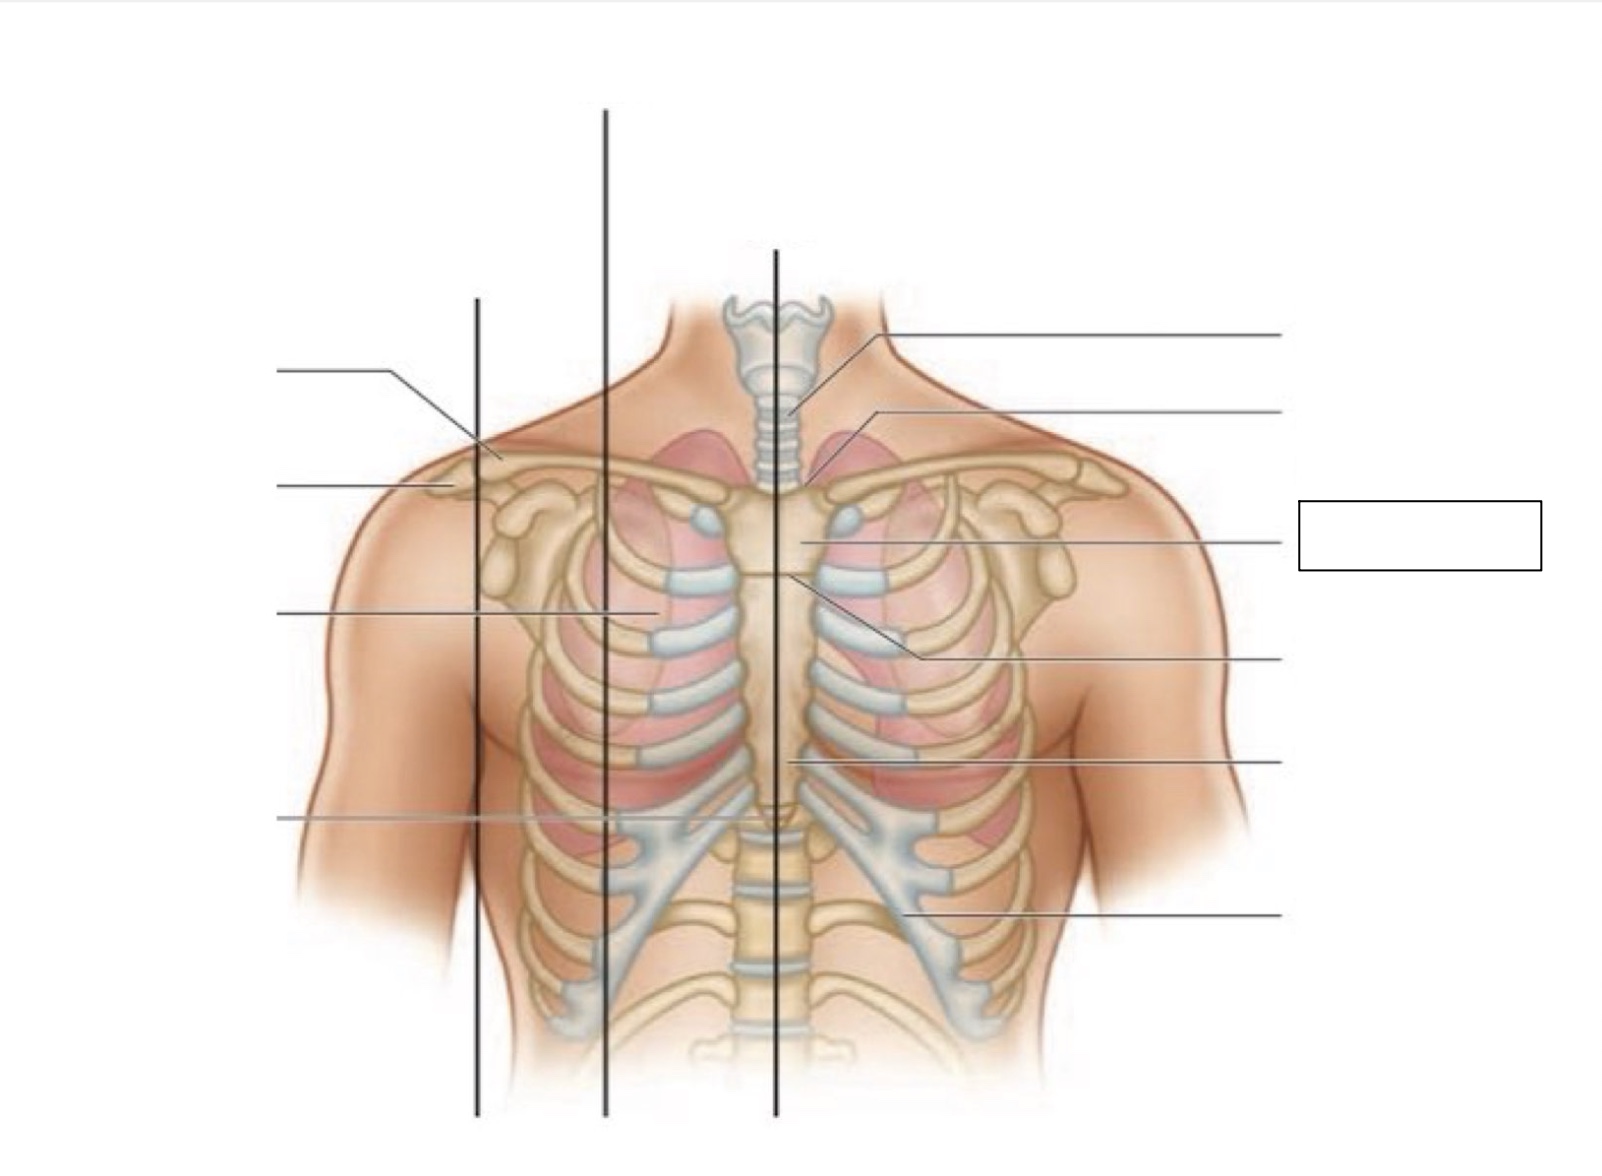

midsternal line

trachea

suprasternal notch

manubrium

angle of Louis

sternum

costal margin

xiphoid process

intercostal space

acromion

clavicle

anterior axillary line

midclavicular line

inferior angle of scapula

scapula

midscapular line

midspinal line

spinous process